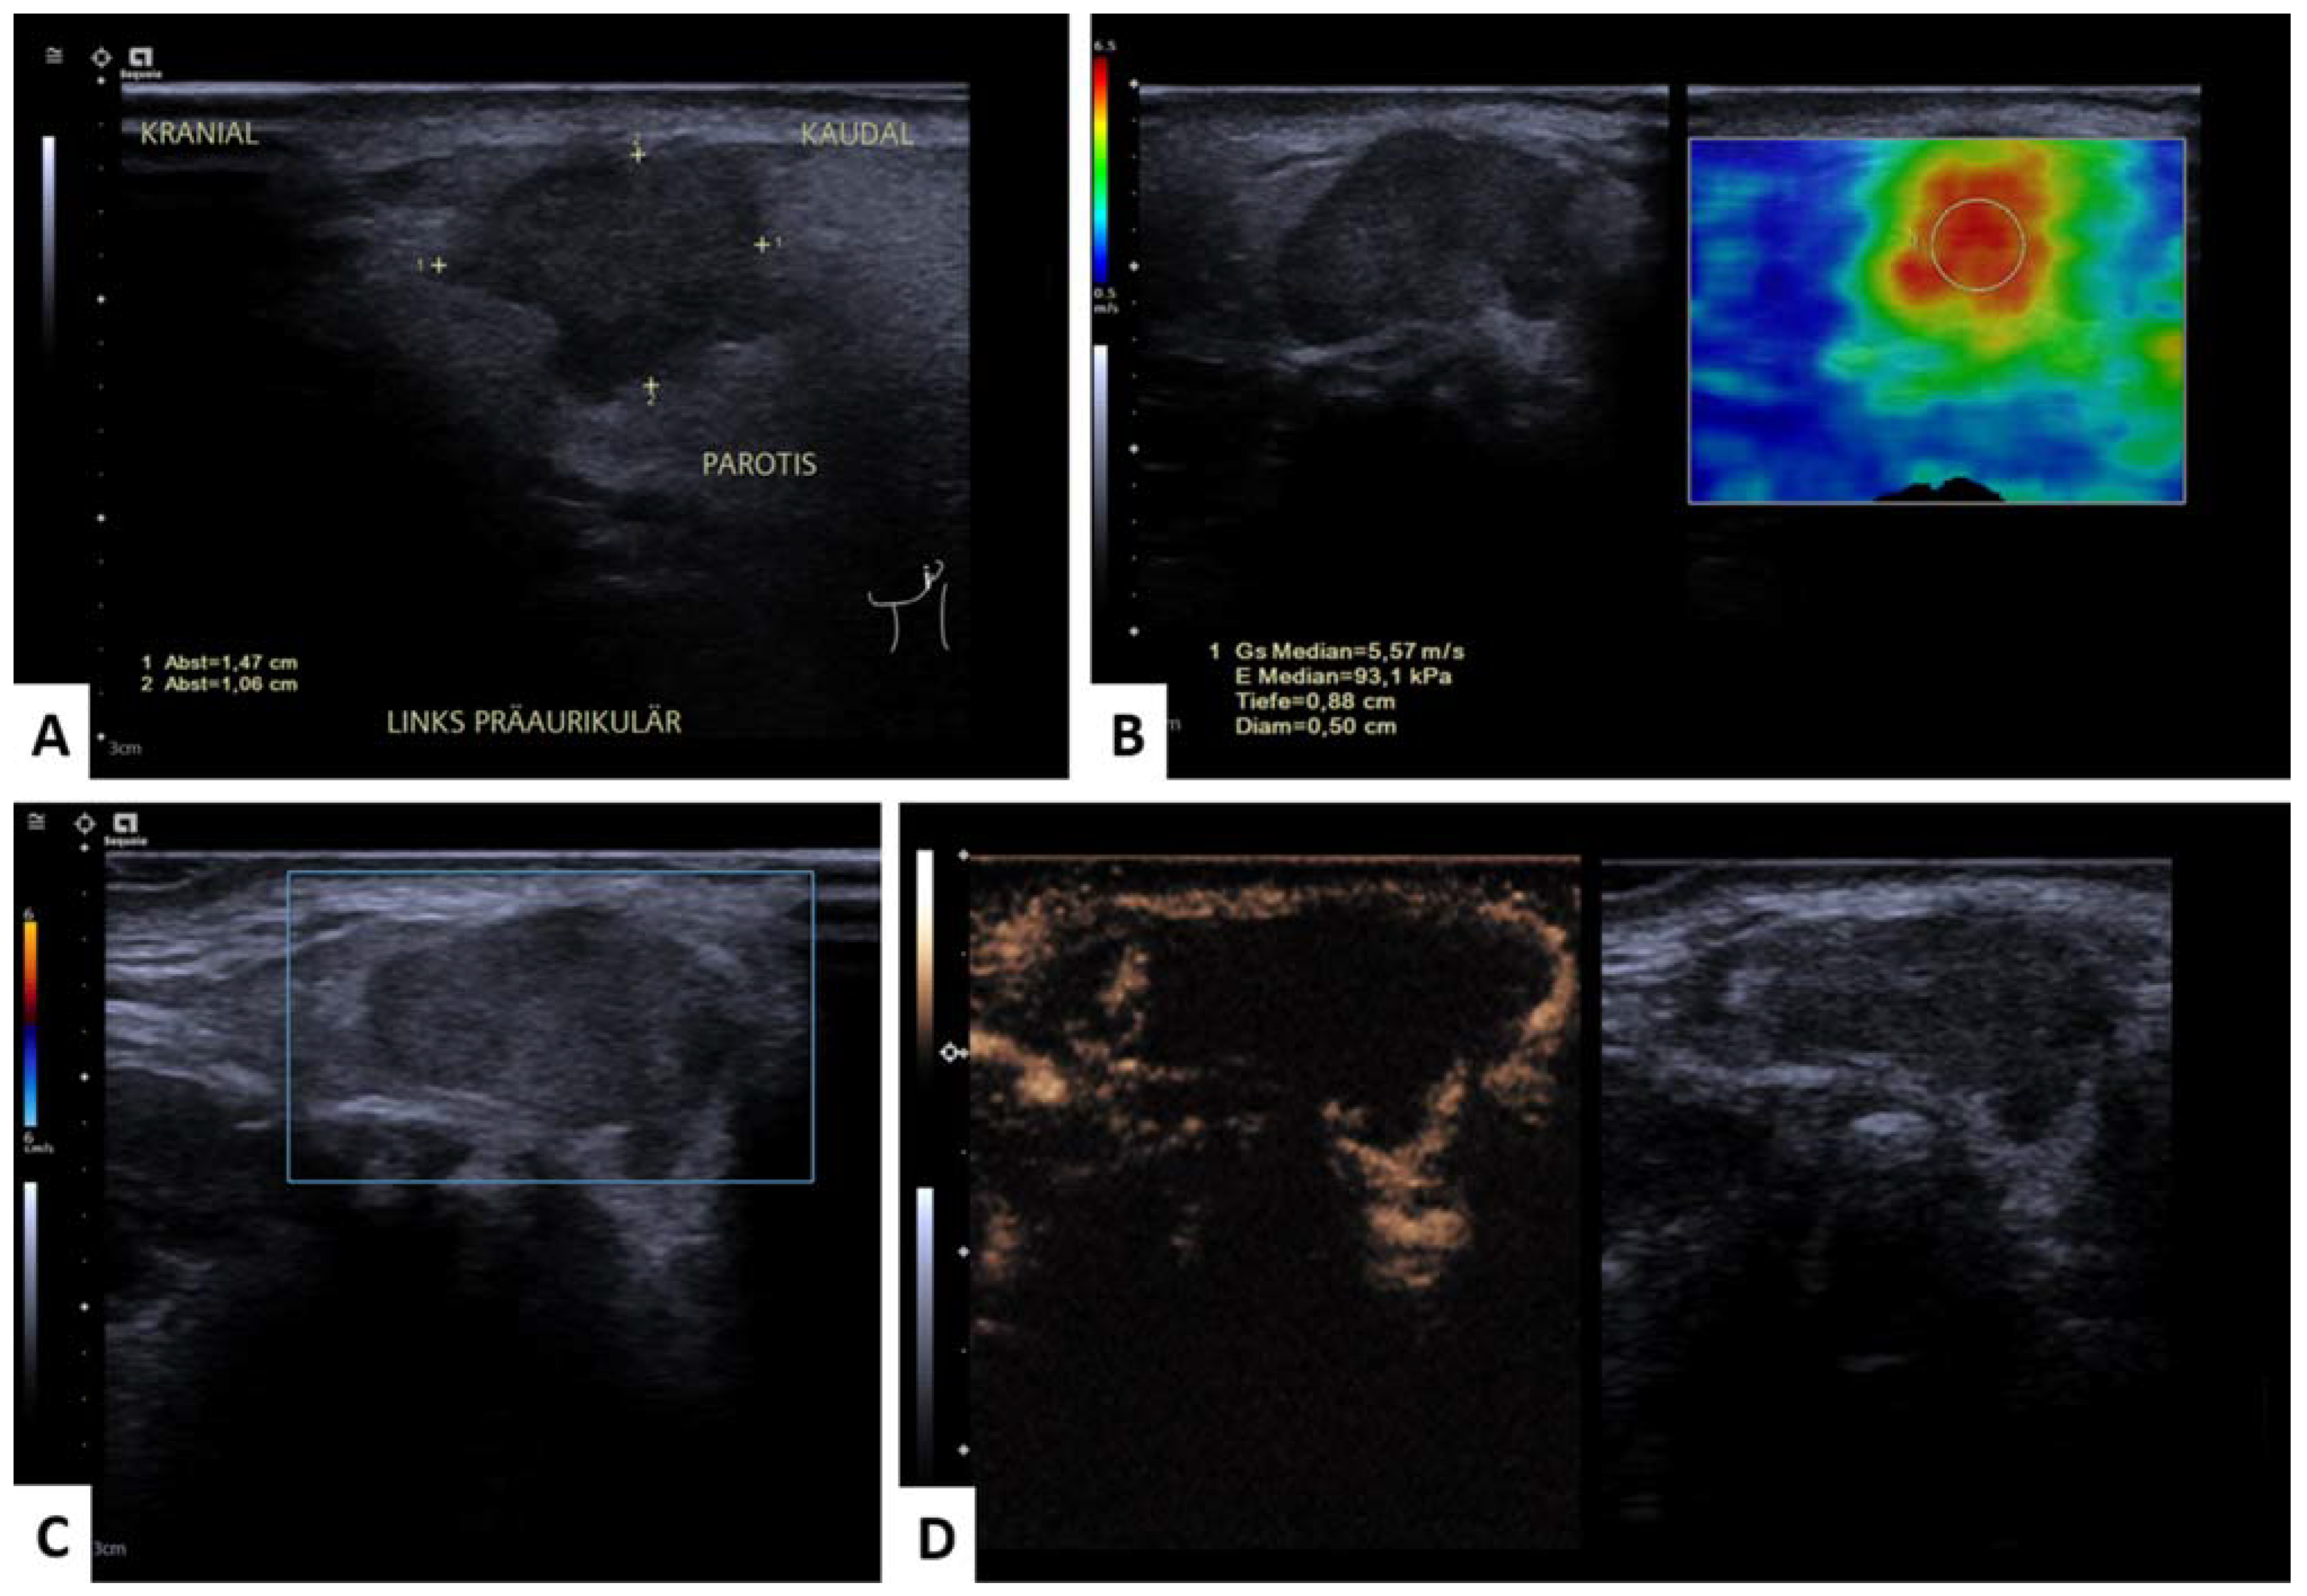

3.4.2. WT versus Malignant Tumors (MT)